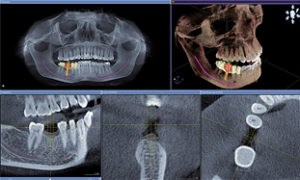

CTの導入により、今までは2次元のレントゲン写真しか撮影できませんでしたが、これからは3次元のCTデータによる診断が可能になります

インプラント治療においては補綴表示とインプラント計画の同時サポートで、新たなアプローチをもたらします。CERECでデザインされたクラウンとCT画像が融合され、一画面上に表示することができるソリューション。これにより、安全性が高くよりシンプルなプランニングが可能になります。3Dビューにより、患者さんへの治療計画の説明を画面を見せながらわかり易く行うことが可能になります

インプラント治療だけでなく埋伏歯(親知らず)の抜歯や歯根嚢胞また難治性の根管治療、歯根破折の診断や矯正治療、歯周病の治療などでもより正確な診断を可能にします